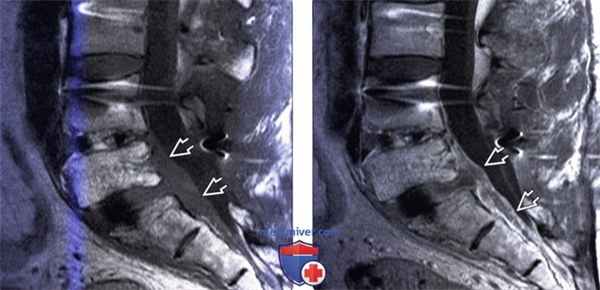

(Слева) Сагиттальный срез, Т1-ВИ: гипоинтенсивный эпидуральный мягкотканный компонент, отслаивающий заднюю продольную связку и распространяющийся от уровня L4-L5 до S2. Тела позвонков, замыкательные пластинки и межпозвонковые диски характеризуются гипоинтенсивностью Т1/гиперинтенсивно-стью Т2-сигнала в острую фазу процесса и гипоинтенсивностью Т1/гетерогенным Т2-сигналом в подострую и хроническую фазы процесса.

(Справа) Сагиттальный срез, Т1-ВИ с КУ: гетерогенное контрастное усиление сигнала мягких тканей вентрального отдела эпидурального пространства, представляющее собой эпидуральный абсцесс на фоне бруцеллезного спондилита.